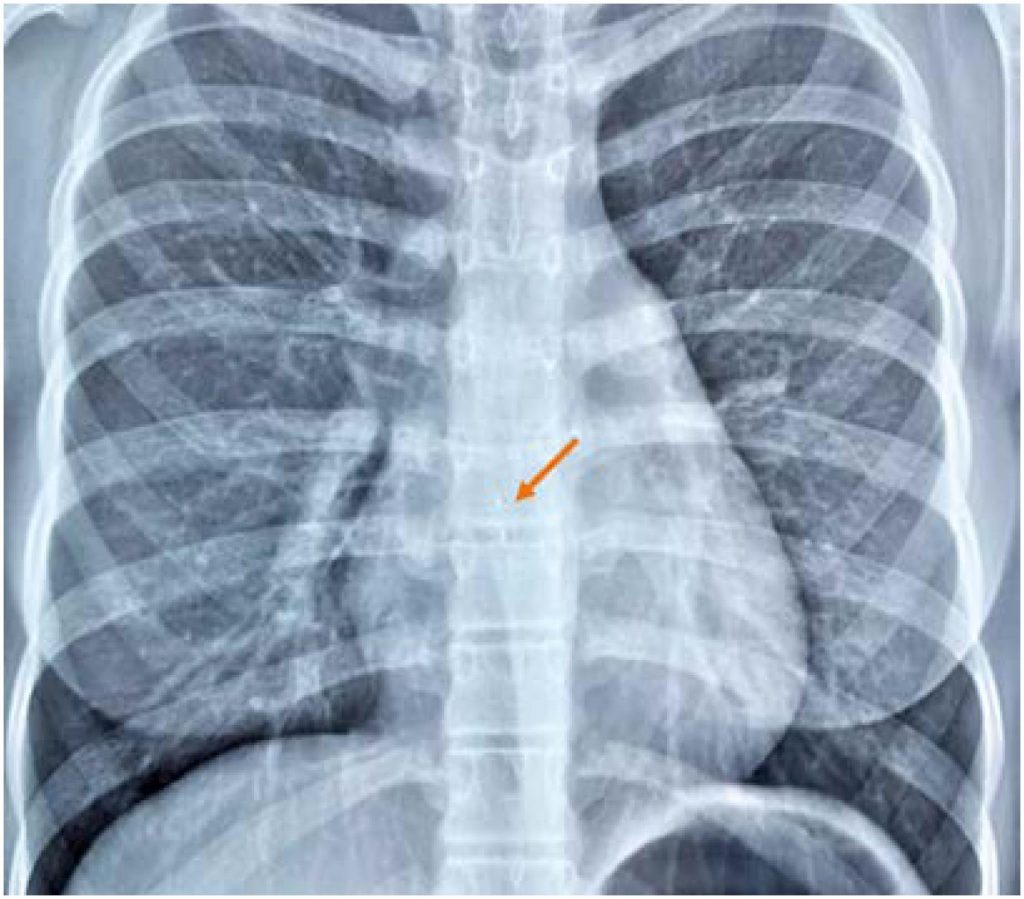

Figure 5

Chest radiography in anteroposterior view. After the procedure, the chest radiography shows prominence of the third arch, denoting pulmonary artery dilation, a prominent pulmonary vasculature, and an image compatible with a metallic device positioned on the topography of the right coronary artery (arrow).